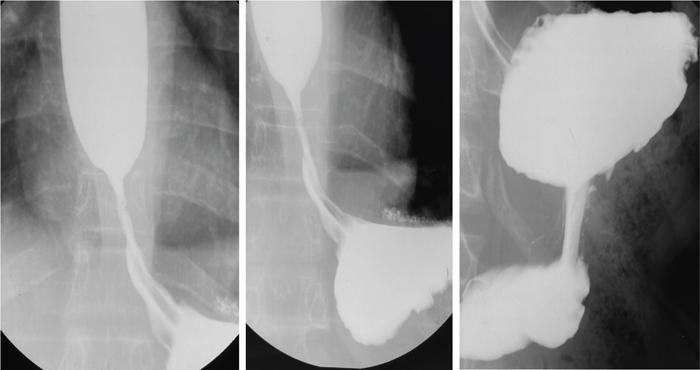

Gaurav Goswami, Gurdarshdeep Singh Madan, Ankita Dhawan Oesophagus is a fibromuscular tube responsible for conduction of food from oral cavity till the level of stomach. It is a hollow structure of approximately 25 cm. Proximal extent of oesophagus, that is cricopharynx begins at the level of C6 vertebral body. At this level, cricopharyngeus muscle merges with inferior constrictor muscle to form a functional zone known as upper oesophageal sphincter (UES). Oesophagus during its course through neck lies posterior to trachea and in thorax lies in posterior mediastinum. In mediastinum, oesophageal body courses to the left of the midline along left atrium, left main bronchus and aortic arch. It returns to the midline at level of T5. On plain radiograph, above T4 level, a sickle-shaped soft tissue shadow is seen overlying the tracheal air – where the trachea abuts the left lung – called the pleuroesophageal line. Similarly, azygoesophageal line is seen on the plain radiograph where the azygous vein and oesophagus abuts right lung (below T4 level). Oesophageal hiatus, present within right crus of diaphragm, is seen at the level of T10 vertebral body. Oesophagus through this hiatus enters the upper abdomen. An approximately 2–4 cm long segment of lower oesophagus is present in the hiatus. This segment shows asymmetrically arranged circular smooth muscles which forms the functional lower oesophageal sphincter (LES). This gastro-oesophageal junction is supported by various ligaments like phreno-oesophageal, gastrosplenic, phrenicolienal and gastrophrenic ligaments. These are responsible for strengthening of gastro-oesophageal junction. However, the most important phreno-oesophageal ligament (or membrane) is responsible for smooth longitudinal sliding of oesophagus through the diaphragmatic hiatus and it also acts as a demarcation between both thoracic and abdominal cavities. Oesophagus is thus anatomically divided into cervical, thoracic and abdominal parts. These parts have different arterial supply, venous supply and lymphatic drainage. Sensory, motor and parasympathetic fibres from vagus are responsible for nerve supply of all the parts of oesophagus. Vagal preganglionic nerve fibres in distal oesophagus are found to terminate within the Auerbach’s (myenteric) plexus. Similarly, Meissner’s plexus acts as a site for afferent impulses within the oesophageal wall. Structural relationship of oesophagus and its implications. These are depicted in Figure 8.1.1: For the purpose of staging of oesophageal cancer (AJCC), oesophagus is divided into upper, middle and lower parts on CT. Upper oesophagus comprises entire cervical oesophagus and thoracic oesophagus till the level of lower border of azygous vein, middle oesophagus from lower border of azygous vein till the lower border of inferior pulmonary vein and lower oesophagus from the lower border of inferior pulmonary vein to stomach including oesophago-gastric junction. The normal oesophageal wall is primarily made of four distinct layers, from inner to outer aspect: Oesophagus shows absence of serosa which is normally present in rest of the organs of GI tract. The distal oesophagus contains two rings – A ring and B ring (Schatzki’s ring) are seen at the proximal and distal to a mild fusiform dilatation of distal oesophagus called vestibule (Fig. 8.1.2). ‘A ring’ also known as muscular ring is present at the proximal extent of vestibule. It represents 4–5 mm band of hypertrophied muscle which can cause constriction at junction of vestibule and oesophageal lumen. It is normally lined by squamous epithelium. ‘A rings’ are rare seen. However, when symptomatic, they cause dysphagia to both solids and liquids. Symptomatic rings are treated endoscopically by dilators and botulinum toxin injection. ‘B ring’ is present at the distal end of the vestibule. It is relatively more common and in most cases seen in association with hiatus hernia. It is a thin membrane of squamous epithelium at its upper surface and columnar epithelium at lower surface. These rings comprise mucosa and submucosa. These rings can be congenital or acquired. Its relationship with GERD is documented. Usually these ‘B rings’ are asymptomatic but they can be symptomatic if they narrow oesophageal lumen to less than 13 mm. Symptomatic rings are treated with either bougie dilatation or mercury weight dilators. CLINICALLY RELEVANT EMBRYOLOGY OF OESOPHAGUS Gurdarshdeep Singh Madan Intrauterine life, especially the first 8 weeks, is extremely busy period in the development of the foetus. Any insult in this period will result in major congenital abnormality and a potentially fatal outcome. One should be mindful of the fact that different anatomically structures are developing simultaneously and not sequentially. Therefore, a specific teratogenic insult caused by drugs/radiation or IU infection like virus results in manifestations in more than one organ system. Over the course of this chapter, we will try to make embryology of oesophagus simple to understand and relate it to the simultaneous development of the respiratory system and embryonal arterial arches and also briefly mentioning their clinical relevance. At around 4th week of intrauterine life, a primordial gut is formed by the invagination of the dorsal yolk sac by lateral embryonal folds and folding of the head and the tail ends. Initially, the gut is a closed tube with oropharyngeal membrane at the cranial end and the cloacal membrane at the caudal end. The oropharyngeal membrane ruptures and orifice is formed around the 26th day. The cranial third of this alimentary system is called the ‘foregut’ (see Fig 8.1.3). Immediately following the formation of the primordial gut, a medial outgrowth develops caudal to the four pair of pharyngeal arches – known as the Laryngo-tracheal groove. By end of the first month (4th week) of intrauterine life, the laryngo-tracheal groove lengthen and protrudes caudally to form laryngo-tracheal diverticulum (LTD). The caudal end of LTD enlarges to form a ‘single’ globular respiratory bud from which both lungs develop. Simultaneously, the longitudinal tracheo-esophageal folds begin to form and start invaginating towards each other. By the end of the 5th week, the tracheo-esophageal folds fuse to form a complete partition, dividing the primitive foregut into ventral laryngo-tracheal tube and dorsal primordial pharynx and oesophagus. The laryngo-tracheal tube opens into the pharynx through a small opening known as the primordial laryngeal inlet (see Fig 8.1.4). Initially after its formation, the length of oesophagus is very short relatively as compared to the total length of primordial gut. However, the oesophagus elongates rapidly as compared to rest of the gut to attain postnatal relative length by the 7th week. During this time, the lumen of oesophagus is obliterated by proliferating epithelium and mucosal glands, which are derivatives of the endoderm. The recanalization of oesophagus is completed by end of the 8th week. The muscles of oesophagus are striated in superior third and derived from the mesenchyme of the fourth and the sixth pharyngeal arches. (Note: Fifth pharyngeal arch disappears.) The inferior third of oesophagus has smooth muscles developed from the splanchnic mesenchyme. The mid third of the oesophagus shows gradual change from striated to smooth muscles. The change from striated to smooth muscles in the oesophageal wall roughly corresponds to the level of arch of aorta in an adult. It must also be noted that both striated and smooth muscles of oesophagus are supplied by the vagus nerve (CN X) which is the nerve of fourth and sixth pharyngeal arches. The chart below illustrates the simultaneous development of pharyngeal arches, respiratory and alimentary system and briefly outlines the development of arterial tree (see Flowchart 8.1.1). The schematic diagram of the embryonal basis of congenital oesophageal abnormalities is attached below. The details of congenital anomalies are covered in relevant chapters (see Flowchart 8.1.2). IMAGING TECHNIQUES – OESOPHAGUS Gurdarshdeep Singh Madan Oesophagus like most other organs of the body may develop ailments – both benign and malignant. They may be congenital, presenting in neonatal period or later in life. The diseases may be structural affecting mucosa; they may also spare the mucosa or could be a transient motility disorder. Hence, the investigation chosen should have maximum cost-benefit to the patient as well as present minimum risk to the patient with judicial use of radiation. With advent of upper gastrointestinal endoscopy, it has replaced radiological studies as preferred investigation for multiple presentations. However, the utility of the radiological studies cannot be discounted due to their ability to provide information regarding motility as in upper gastrointestinal contrast studies and cross-sectional data for cancer staging. During the course of this chapter, we will discuss in brief various imaging modalities and techniques. Though endoscopy has largely displaced imaging studies as initial investigation of choice for dysphagia, their role in motility disorders is limited. Endoscopic ultrasound is investigation of choice for evaluating T1 and T2 oesophageal Ca. PET-CT is functional imaging which is gold standard in evaluating distant metastasis. CT scan is initial staging investigation for T3 and T4 disease and provides valuable information in preoperative planning and postoperative assessment. Contrast oesophagogram done with correct technique is an important investigation for evaluation of motility disorder and is a competent investigation in evaluation of structural/mucosal disorders. The choice of the imaging modality to evaluate a patient depends on patients’ condition, clinical suspicion and the risk benefit ratio to the patient. In a resource constraint setting, availability and affordability of the investigation is also equally important. Many international societies have propounded the guidelines for first investigation of choice. American College of Radiology appropriateness criteria (ACR-AC) for imaging studies in evaluation dysphagia has been adapted as Table 8.1.1. The investigation of choice in other clinical settings are covered in the respective chapters. Fluoroscopic biphasic oesophagogram Fluoroscopic single contrast oesophagogram Oesophageal transit nuclear medicine scan Fluoroscopic modified barium swallow CT neck and chest with or/and without IV contrast Fluoroscopy pharynx dynamic and static imaging Fluoroscopic biphasic oesophagogram Fluoroscopic single contrast oesophagogram Fluoroscopic modified barium swallow Oesophageal transit nuclear medicine scan CT neck and chest with or/and without IV contrast Fluoroscopy pharynx dynamic and static imaging Fluoroscopic single contrast oesophagogram CT neck and chest with IV contrast CT neck and chest without IV contrast Oesophageal transit nuclear medicine scan CT neck and chest with and without IV contrast Fluoroscopy pharynx dynamic and static imaging Fluoroscopic modified barium swallow CT neck and chest with IV contrast Fluoroscopic single contrast oesophagogram Fluoroscopic modified barium swallow Fluoroscopic biphasic oesophagogram Oesophageal transit nuclear medicine scan CT neck and chest with or/and without IV contrast Fluoroscopy pharynx dynamic and static imaging Mazzeo et al. and Carrascosa et al. have described technique of virtual oesophageal endoscopy with use of air insufflation via catheter inserted into the upper oesophagus and by use of effervescent agents like those used in fluoroscopic oesophagogram. However, despite these technological assessments, the sensitivity of CT scan in identifying T1 and T2 disease is limited. The CT scan is also limited in identifying normal-sized metastatic lymph node. The limitation can only be partially addressed by using morphological appearance like extracapsular spread and central necrosis. National Comprehensive Cancer Network (NCCN) guidelines for oesophageal and oesophagogastric Ca recommends CECT chest and abdomen with oral and IV contrast in staging assessment of cancers T3 and above. CT is indicated in assessment of early and delayed postoperative complications. Lantos et al. and Upponi et al. have demonstrated slightly better sensitivity of CT in detecting early postoperative complications. However, it is marred by poor specificity in the same period. In delayed postoperative dysphagia, use of CT oesophagogram has demonstrated increase in sensitivity in identifying recurrent disease, abnormality caused by surgical hardware/technique or a late onset seroma. CT oesophagogram (Table 8.1.3) can be performed by preparing 3% iodinated contrast in water or thickening agent like Simply Thick to form a honey- or nectar-like consistency swallowed on the table with last gulp taken immediately prior to the acquisition. The images are reconstructed in curved multiplanar reformats in soft tissue window. MRI and MR oesophagogram – Quint et al. was the first, however, unsuccessful attempt evaluation of oesophagus on a 0.35T MRI, 35 years back. Since then, there has been substantial advancement in the MRI technology with evolution of quicker and dynamic sequences, and advancement of k space filling technology leads to further shortening of scan times. Yamada et al. used MRI in vitro staging of Ca oesophagus with 4.7 T MRI in 1997. Subsequently, high-field MRI up to 7T have been used in evaluation oesophageal specimen and advanced MRI imaging techniques like diffusion tensor MRI and tractography have been used. In spite of these advancement in evaluation of ex vivo specimen, the advancement and utilization of MRI for clinical purposes has been gradual and sparse. In 2005, Riddell et al. used surface coil MRI in staging of oesophageal carcinoma. Sakurada et al. showed promising results in staging of T3 and T4 Ca oesophagus patients using T2WI and DWI. Over the recent years, the advancements in in vivo MRI of oesophageal Ca have been focused on identification of lymph nodal involvement (Alper et al.), staging postconcurrent radio-chemotherapy (Wang et al.), postoperative nodal recurrence (Shuto et al.) and gross tumour volume delineation (Hou et al.). Pavone et al. (1992) used Gadopentetate dimeglumine – barium paste in distending and opacifying and assessment of concentric/eccentric tumour growth in patients of Ca oesophagus and identifying a case of oesophageal leiomyoma in their study. In 1996, Ogawa et al. used ferric ammonium citrate-cellulose paste for oesophageal lumen opacification with excellent luminal opacification in 84% of the sagittal images and 79% of the axial images. Subsequently, Zhang et al. (2012) utilized high T2* signal of water to provide good contrast in MR oesophagogram. For easy intake of water, the head of patients was padded slightly high and water swallowing was done through a pipe/straw and patients were instructed to swallow the water continuously during the acquisition. Without respiratory triggering, sagittal and axial True fast imaging with steady state procession (True FISP) T2*weighted images were obtained. The diagnostic quality of water swallow was graded excellent in 97.7% of the sagittal images and in 81.8% of the axial images the cases. Even after the advances elucidated above, the present utility of MRI in diagnosis of oesophageal disease is more as an occasional adjunct for resolving specific clinical dilemmas rather than as a primary investigation. However, the future of the modality is bright and promising with continuous improvement in acquisition technology and the hardware. EUS is a specialized endoscope with an ultrasonographic probe to evaluate hollow visceral organs. It is useful to visualize oesophagus and stomach lining. Adjacent organs can also be visualized like liver, pancreas, GB, para-aortic region and mediastinum. EUS is done under mild sedation. EUS is available in two types of probes, that is Linear and Radial Probe. Gastrointestinal tract is visible in a healthy patient as five layers. These are first layer – superficial mucosa, second – mucosal, third – submucosal, fourth – muscularis propria and fifth – oesophageal adventitia. EUS is helpful mainly in characterizing the lesion as benign or malignant. On a standard endoscopy study, these lesions are usually seen as a bulge within wall. EUS helps in determining the location of lesion, whether it is within wall or outside the wall. Also it helps in determining the extent of involvement of lesion and its relationship with surrounding structures. It also has a role in looking for secondary causes of motility disorder like achalasia. However, its diagnostic as well as therapeutic role in oesophageal cancer is noteworthy. Endoscopic ultrasound plays a vital role in local staging of oesophageal cancer. Staging of oesophageal cancer is essential to choose appropriate therapy. Surgery is the gold standard for staging of oesophageal cancer. Usually in clinical practice, most patients undergo preoperative therapy as chemoradiation which is followed by surgery. Thus, for pretreatment staging, EUS findings are complementary with radiological imaging like MRI, CT scan and PET scan. Standard protocol is to perform EUS in most cases of oesophageal cancer. EUS is useful in early stages of oesophageal cancer, that is T1a and T1b. It is helpful in evaluating lymph node enlargement. Whenever a patient is assessed for feasibility of early cancer for mucosal resection via endoscopic procedure, it is important to rule out deeper tissue invasion and lymph node metastasis. EUS also plays essential role in lymph node FNA and biopsy in doubtful lesions. Role of EUS in advanced oesophageal cancer is limited. Usually EUS cannot be used to differentiate between T3 and T4. Distant metastasis is usually well diagnosed on cross-sectional imaging. EUS can only detect invasion into aorta as T4 which is better visualized in CT scan. EUS has limitations like it cannot look into metastases where CT scan and PET scan are useful. Role of EUS in postradiation or chemotherapy is under evaluation. EUS is technically difficult and has a significant learning curve. ALGORITHMIC APPROACH TO A PATIENT WITH OESOPHAGEAL DYSPHAGIA Gurdarshdeep Singh Madan, Ankita Dhawan Swallowing is essential not only for maintaining the nutrition for life but also a major determinant in one of the pleasures of life. The voluntary component of swallowing is the initial 10% and is initiated by collecting the food bolus onto the tongue and voluntarily propelling the bolus into the oropharynx. This initiates a wave of involuntary contraction and relaxation of pharyngeal muscles which pushes the food through cricopharynx into the oesophagus. Closure of glottis and cessation of respiration are reflex activities. Thereafter, the ‘peristaltic’ ring of oesophageal muscle contraction pushes the food towards the stomach at a rate of approximately 3.0–4.5 cm/s. The semisolid and liquid food falls by gravity, ahead of the peristaltic wave when the individual is upright. In cases where there is incomplete clearing of the oesophagus, secondary peristaltic waves are generated which are weaker than the primary peristaltic wave and aid in clearing the oesophagus. Unlike the rest of oesophagus, lower oesophageal sphincter (LES) is contracted at rest and relaxes on swallowing, which prevents reflux of gastric contents into the stomach while permitting the food bolus into the stomach (Fig. 8.1.7). Difficulty in swallowing is a common problem affecting approximately 3%–15% of general population. This prevalence increases in elderly population and in patients with other comorbidities. Understanding the symptomatology and pathophysiology of dysphagia is essential for the radiologist to plan the correct investigation and to remain clinically relevant in management of the patient. The symptoms of difficulty on swallowing has been further classified into various terminology, each highlighting a specific association and hence clinically leading to a smaller set of differential diagnosis (Table 8.1.4). Depending on location, dysphagia may be localized to oral, oro-pharyngeal or oesophageal regions. Dysphagia can also be subclassified as Structural dysphagia – caused by mismatch between the size of food bolus and the lumen of the aerodigestive track/oesophagus that is a large food bolus or the narrow lumen. It is classically described as difficulty in swallowing solid food. Motor dysphagia – it is caused by abnormalities of peristalsis/impaired upper oesophageal sphincter relaxation/closure and impaired lower oesophageal sphincter relaxation. It is difficulty in swallowing both solid and liquid foods. There are certain limitations to such generalization of symptoms. For example, Scleroderma, which is primarily an oesophageal motility disorder, presents initially with mild dysphagia on swallowing solid bolus. Also, in patients with oropharyngeal structural pathology, patient may be more symptomatic and concerned due to inability to handle fluids and causing aspiration. In other subset of patients, more than one mechanism may be responsible causing both improper propulsion of food and associated secondary luminal narrowing by stricture formation. Odynophagia generally arises due to passage of bolus along inflamed or ulcerated mucosa causing irritation, which may be due to foreign body ingestion, infective, chemical or inflammatory oesophagitis. Associated symptoms like cranial nerve abnormalities, hoarseness and other general and systemic symptoms and signs may point towards the location and cause of dysphagia. The patient may be able to localize the location of dysphagia. However, the sensation of dysphagia in oesophagus (especially in distal two-thirds) may be proximally referred in a third of the cases. Inability to produce sufficient saliva (Xerostomia) may also be perceived as dysphagia, especially common in elderly (see Fig. 8.1.8). Adult oesophagus measures approximately 17–26 cm in length and extend from cricopharynx to the lower oesophageal sphincter. Oesophagus can be anatomically divided into cervical oesophagus (cricopharynx to suprasternal notch) and thoracic oesophagus. The structural causes of the dysphagia manifest when the lumen of the oesophagus has been reduced to one-third (~13 mm in size). Dysphagia in a setting of Gastro-oesophageal Reflux Disease is very common and is multifactorial in pathophysiology – increased mucosal sensitivity, impaired distensibility and motor function, formation of strictures. Propulsive/motor disorders can be due to abnormality of peristalsis (both excessive and reduced) or relaxation of lower oesophageal sphincter (see Figs. 8.1.9–8.1.13). Few common causes of oesophageal dysphagia are enumerated below: Presentation and causes of dysphagia in neonates and infants tend to be different from adults. They may present as aspirations, incessant crying in addition to choking and inability to feed. In neonates, the causes may be neuromuscular or central in origin affecting swallowing or could be congenital in nature affecting oral or pharyngoesophageal phase of swallowing (Fig. 8.1.14). In older children and toddlers, ingestion of foreign body is one of the most common cause of dysphagia/choking. In these cases endoscopy is therapeutic. Ingestion of caustic agents can cause severe caustic oesophagitis which can be potentially fatal. In children, high index of suspicion should be present and relevant history for ingestion of caustic agents should be elicited. Other causes of dysphagia (Fig. 8.1.15) in paediatric age group are covered in detail in relevant chapters. Which investigation to choose: The armamentarium available for a clinician while evaluating dysphagia are mentioned below: Before the advent of flexible upper gastrointestinal endoscopic techniques, contrast (barium) upper gastrointestinal radiological studies especially barium swallow were the cornerstone in evaluating dysphagia. However, endoscopic examination of the oesophagus is presently the first line investigation of choice for oesophageal dysphagia. Endoscopy offers the advantage of mucosal assessment and characterization, ability to identify Barrett’s metaplasia and offer diagnostic and therapeutic interventions in a single sitting. Endoscopy is relatively deficient in diagnosing motility disorders and identifying benign conditions which cause dysphagia but do not cause mucosal abnormalities. Barium swallow should be done as a first line investigation of choice where dysmotility or oesophageal ring/webs/subtle strictures are suspected. A well-planned barium study with barium-coated appropriate bolus such as bread/marshmallow/barium pill may demonstrate oesophageal ring causing hold up of contrast. Barium swallow is also the first line investigation of choice for Achalasia. It may also be used for characterization of hiatal hernia. Oesophageal manometry/HRIM (high resolution impedance manometry) is specifically done in patients in whom endoscopy and barium studies are noncontributory. They show high pressure at upper and lower oesophageal sphincter with mid oesophagus showing waves of peristalsis. It is the gold standard to diagnose achalasia with certainty. It is also of immense value in diffuse oesophageal spasm and nutcracker oesophagus. Endoscopic ultrasound combines the advantage of an endoscope with high-frequency ultrasound, providing improved spatial resolution, which is useful for staging of oesophageal carcinoma and allows taking directed biopsies for histopathology. It can also be used to assess Barrett’s metaplasia and evaluating other submucosal tumours/paraoesophageal lymph nodes. PET-CT scan is a preferred modality of oesophageal and oesophago-gastric junction Ca and includes PET CT from skull base to mid-thigh in absence of M1 disease. Early disease may not be detectable on PET-CT as depth of invasion cannot be accurately assessed. Assessment of locoregional lymph node is limited as uptake from oesophageal lesion cannot be differentiated from uptake from periesophageal lymph nodes due to limited spatial resolution of PET. Nonregional or distant lymph node involvement can be well identified and assist in accurately upstaging and planning treatment of Ca oesophagus. CT scan has limited value in identifying early oesophageal Ca and identifying nonregional lymph nodes. It can be used in assessing recurrence and to check for integrity postoesophagectomy. Ambulatory reflux monitoring is useful in diagnosing GERD without oesophagitis. Endoscopy is normal in these patients with hypersensitive oesophageal mucosa – causing pain. The electrode tip is placed in distal oesophagus and pH is measured over 24/48 hours. The outcome is expressed as percentage duration when the distal oesophageal pH was less than 4. This can be combined with impedance monitoring to increase sensitivity. They also serve as a guide to evaluate poor response to therapy for GERD. A reading of more than 6% is considered abnormal. Additional newer advances like use of Functional Lumen Imaging Probe (FLIP) has been evaluated to assess oesophagogastric junction distensibility and distension-mediated peristalsis in oesophageal motility disorders. The investigations are often guided by clinician’s preferences, availability of the investigation and likelihood of a probable diagnosis on history taking and clinical examination. OESOPHAGEAL MOTILITY DISORDERS Ankita Dhawan Oesophagus is around 25–40 cm muscular tube in posterior mediastinum. It comprises both striated and smooth muscles. It extends from the level of upper oesophageal sphincter (UES – at the level of cricopharyngeal muscle) and lower down till the level of lower oesophageal sphincter (LES – present at the junction of lower end of oesophagus and cardia of stomach). Normal function of oesophagus is to transport both solids and liquids to stomach, which is mainly attributed to oesophageal peristalsis and gravitational force. Therefore, radiographic evaluation of oesophageal peristalsis is done in recumbent position to remove the contribution from gravity.